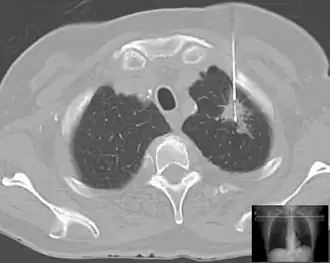

For easily detected and accessed sites, any suspicious lesions may be assessed. Originally, this was skin or superficial masses. X-ray, then later CT, MRI, and ultrasound along with endoscopy extended the range.

| Lung | Biopsies of the lung can be performed in a variety of ways depending on the location. |